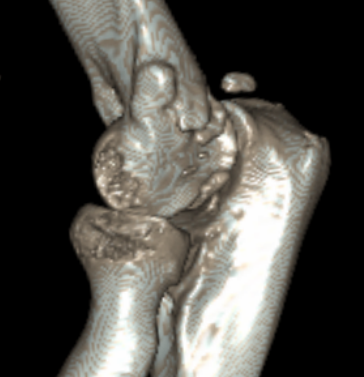

Multiple elbow loose bodies

lblblb